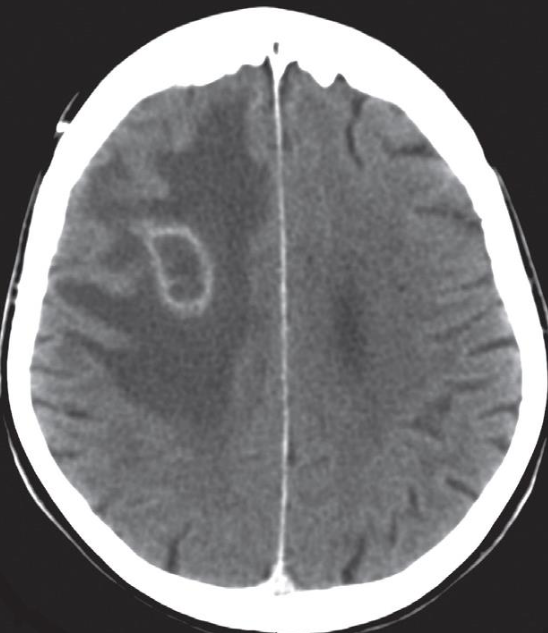

A. Give the name of the pattern of contrast enhancement of the lesion

- Contrast CT*

B. Give ONE cause for the pattern of contrast enhancement shown Enhanced lesion: Lesion which shows contrast uptake

- Homogenous

- Ring

- Serpigenous [AVM]

A. Give the name of the pattern of contrast enhancement of the lesion in the given image

. (a) Post contrast CT scan showing a right frontal low density ring-enhancing lesion with surrounding vasogenic oedema

B. Give ONE cause for the pattern of contrast enhancement shown in the given image Cerebral abscess